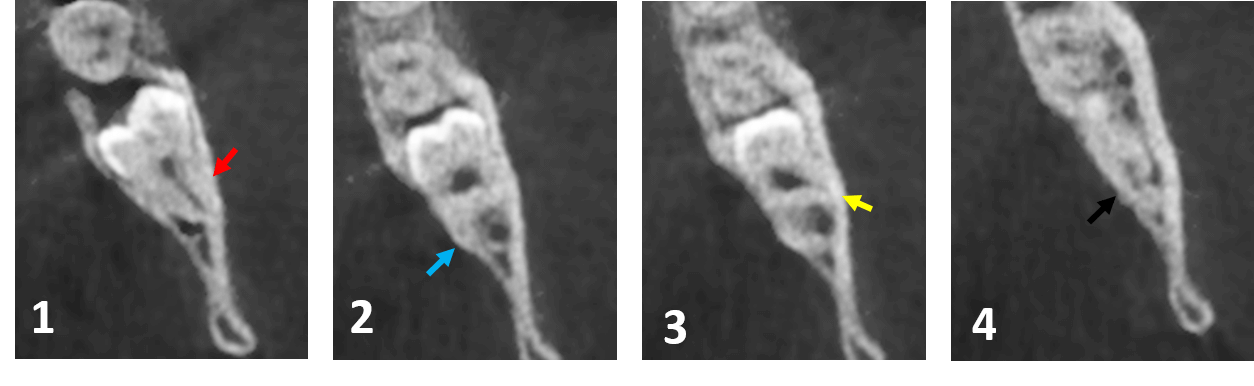

Fig.2

En los cortes axiales del órgano dentario 38 (Fig.2) se observa la multiplicidad en el número de las raíces. En lo diferentes cortes se enumeran el número de las raíces, y se señalan con diferentes colores.